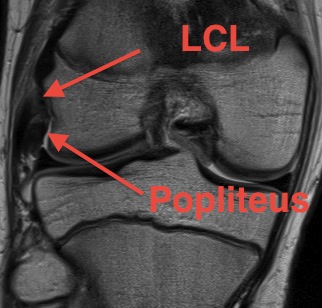

Lateral collateral ligament anatomy

Don't see entire length on single MRI

- use coronal to look for origin from lateral epicondyle above popliteal insertion

- use coronal to look for insertion onto anterolateral fibular head

Popliteus anatomy

Don't see entire length on single images

- coronal image to see insertion onto popliteal fossa below LCL

- follow tendon around on coronal images

Normal anatomy

Popliteofibular ligament anatomy

Normal anatomy